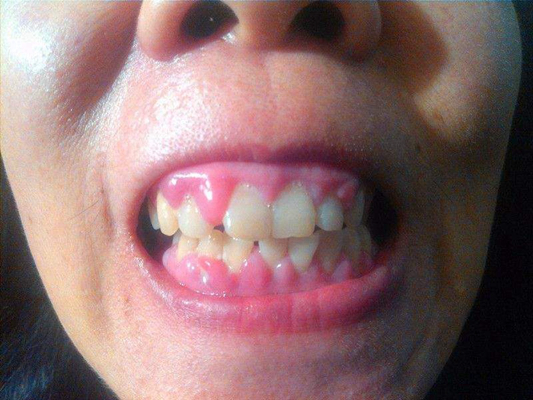

牙齦炎

牙齦炎圖片

牙齦炎和牙周炎